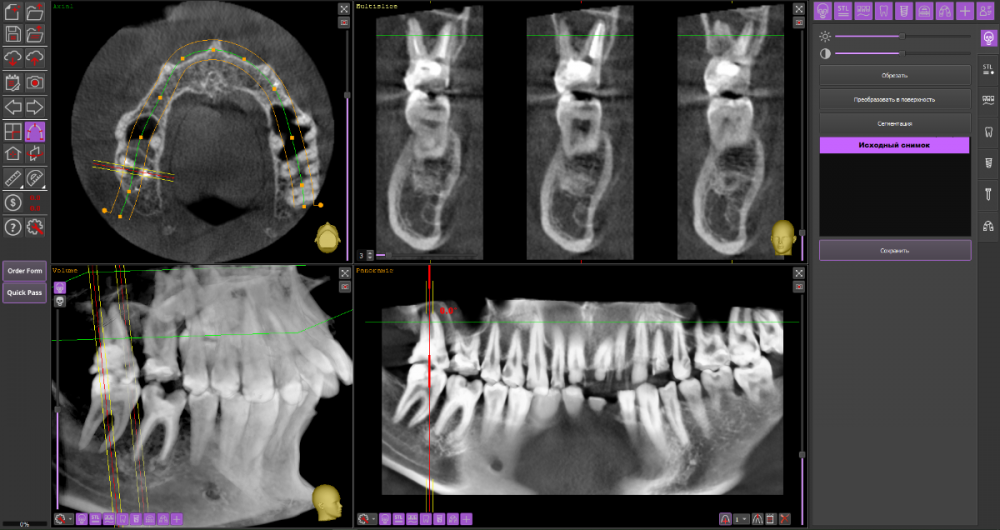

Добрый вечер, уважаемые специалисты. Подскажите, пожалуйста, есть ли возможность избежать удаления верхней 6-ки справа и использовать культевую вкладку + коронку для протезирования? Заранее спасибо за ответы. КТ: https://drive.google.com/drive/folders/17DOY2HNbp9x-5vxpit8V9hBL8D88hrAt?usp=sharing

16_1.thumb.png.bb12ffa7175f4bd0f7f85bb8f69ea174.png

16_2.thumb.png.9dafe1ce7b90f3a15660ac669b24eb3e.png

На мой взгляд, зуб 16 вполне можно сохранить при условии адекватного лечения корневых каналов.

А вот зуб 17 перелечить маловероятно.